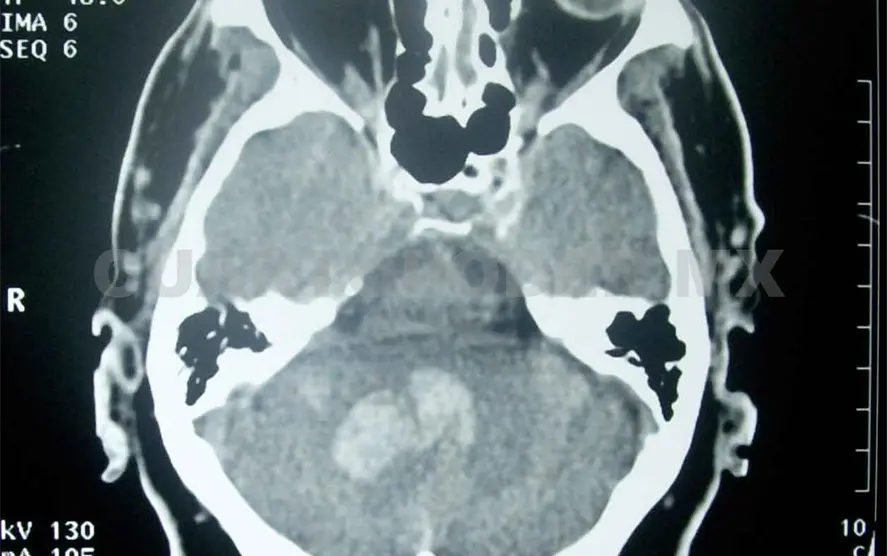

De acuerdo al Centro Nacional de Neurología y Neurocirugía “Manuel Velasco Suárez”, existen tres tipos de EVC: trombótico, embólico y hemorrágico; el primero se origina por los depósitos grasos en las arterias, lo que causa la formación de coágulos como consecuencia del estrechamiento de los vasos sanguíneos.

En el caso del EVC embólico, el coágulo se forma en otras partes alejadas del cuerpo, parte de esa formación conocida como “émbolo” es arrastrado hacia el cerebro hasta que tapa un vaso sanguíneo y corta el abastecimiento de sangre ocasionado una embolia.

Por último está el tipo hemorrágico o derrame cerebral, causado por la ruptura y sangrado de un vaso sanguíneo en el cerebro. En todos los casos las señales de alarma, además de las que enlistó doña María, son visión borrosa, mareos repentinos, dolor de cabeza intenso e incapacidad para comunicarse de cualquier forma.